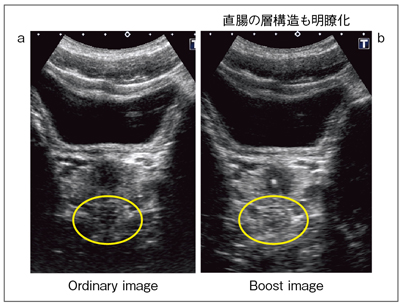

もうひとつの超音波の「視点を変える」方法として,東芝メディカルシステムズと開発中の,高分解能で高ペネトレーション画像を実現する“Boost Image(仮称)”について臨床画像を紹介する。

図8 aは,従来のAplioの7MHzリニアプローブで撮像した脾動脈瘤だが,アーチファクトや減衰があることがわかる。これをBoost Image(図8 b)で見ると,横隔膜のラインもきれいに描出され,浅部から深部まで高分解能のままでペネトレーションがとれていることがわかる。また,正常な膀胱-前立腺-直腸の画像(図9)では,非常に深く見にくい直腸の層構造が,Boost Imageでは明瞭化している。超音波による消化管検査を行う場合,深部の直腸の評価には難渋するが,その意味でもBoost Imageへの期待は大きい。

Boost Imageは,画像上の効果としては分解能が高くペネトレーションが良いということで,ある意味では超音波にかかわるものが夢に描いていた画像だと言える。Boost Imageでは,S/N比も向上しコントラストの改善も図れる。

将来への期待としては,深部に存在する微細病変の診断能の改善が期待されるほか,今まで困難だったtough patientの診断精度の向上や,検査者としてはプローブの交換回数が減少することを期待している。現段階では改善すべき点もあるが,従来の分解能とペネトレーションというトレードオフに対して,視点を変えたブレイクスルーが期待される。